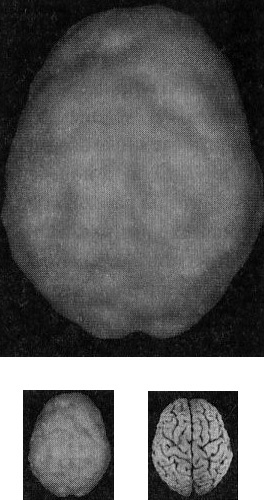

Когда мозг работает правильно, у вас все хорошо Когда мозг не в порядке, в жизни начинаются неприятности Именно мозг определяет эффективность вашей жизни. Этот принцип выглядит простым, но на самом деле он достаточно неоднозначный и может вызвать тревожность. Основная идея заключается в том, что мозг должен функционировать оптимально. Когда он работает правильно, вам легче оставаться эффективным родителем, ребенком, партнером, другом, коллегой, менеджером или общественным деятелем. Когда мозг функционирует правильно, вы имеете полный доступ к своему истинному Я. С другой стороны, если мозг болен, начинаются трудности в работе, отношениях, наедине с собой и в компаниях. Становится труднее проявлять свои лучшие качества и сильные стороны, нередко люди действуют вопреки своим ценностям, целям и представлениям о нравственности. Принцип 2 Когда мозг работает правильно, у вас все хорошо. Когда мозг не в порядке, в жизни начинаются неприятности Я вывел этот принцип в результате интерпретации сотен томограмм моих пациентов, поскольку не только читаю сканы, но и напрямую работаю с людьми и их семьями, изучаю историю их жизней. Уже в самом начале моей работы с томографией стало очевидно, что существует зависимость между качеством функций мозга на сканограммах и умением моих пациентов принимать решения, ставить цели и поддерживать отношения. Анализируя снимки, я стал размышлять о разнице между двумя типами поведения, которые я называю волевым поведением (управляемым силой воли) и мозговым поведением (управляемым неконтролируемыми импульсами мозга). Реализовывать команды силы воли возможно только при здоровом мозге, поскольку лишь он позволяет людям делать осознанный выбор и в любой ситуации действовать себе во благо. Волевое поведение продуктивно, оно способствует достижению целей, которые вы сами поставили. Например, приняв решение поступить в медицинский институт, человек должен очень усердно учиться, чтобы выдержать сложные экзамены. Прежде чем объяснить, что такое «мозговое поведение», я хочу сделать небольшое отступление, чтобы рассказать о томографии, которую мы проводим в наших клиниках. Она называется ОЭКТ — однофотонная эмиссионная компьютерная томография — и относится к области ядерной медицины, то есть для оценки кровообращения и схем активности мозга используются крошечные дозы радиоизотопов. Сканограммы ОЭКТ отличаются от типичных анатомических снимков МРТ и КАТ, которые показывают строение мозга. ОЭКТ показывает только степень активности разных областей мозга — то, как он работает. Результаты сканов ОЭКТ очень легко интерпретировать. Нужно посмотреть на области мозга, которые работают хорошо, области, которые функционируют чересчур активно («перегреты») и на недостаточно активные области. Затем мы сравниваем изучаемый скан с большой базой данных здоровых и абнормальных томограмм. В этой книге используют трехмерные снимки мозга двух видов. Первый — это трехмерные снимки поверхности, которые фиксируют верхние 45 % активности мозга. На них показано кровообращение в коре мозга и подкорковых областях. По этим снимкам мы определяем области нормального кровообращения и области со сниженным доступом крови. С помощью таких томограмм выявляют инсульты, травмы и ущерб от наркотиков. Снимок здорового мозга должен показать ровную симметричную активность по всей поверхности коры мозга (рис. 2.1 и 2.2). Трехмерное изображение поверхности здорового мозга ОЭКТ (вид поверхности сверху и снизу) Рис. 2.1 Вид сверху Полная симметричная активность ![]() Рис. 2.2 Вид снизу Полная симметричная активность ![]() Сниженная активность выглядит на подобных сканах как дыра или вмятина. Эти «дыры» и «провалы» не означают, что активность мозга в этих местах совсем на нуле, она просто снижена, так как компьютер настроен показывать только верхние 45 % активности. Все, что меньше этого значения, выглядит как дыра или вмятина. Порог в 45 % выбран, поскольку он соответствует двум стандартным отклонениям от нормы [1] и, согласно нашим данным и данным других исследователей, является оптимальным для диагностических целей. Второй тип томограмм — это трехмерные функциональные снимки, в которых компьютер сначала вычисляет среднюю активность мозга, а затем показывает верхние 15 % активности. Они помогают увидеть гиперактивные области, что полезно в диагностике припадков, разных типов тревожности и депрессии. Здоровый трехмерный функциональный снимок (рис. 2.3 и 2.4) должен показывать активность (белым цветом) в задней части мозга (мозжечке) и визуальной, или затылочной, коре и среднюю активность в остальных местах (показано сеткой). Трехмерное изображение функциональной активности здорового мозга ОЭКТ (вид поверхности сверху и снизу) Рис. 2.3 Вид сверху ![]() Рис. 2.4 Вид сверху ![]() Примечание: В тексте книги будут использоваться иконки, которые помогут читателю понимать сканограммы и увидеть их отличия от нормы. Рис. А состоит из двух иконок: трехмерного изображения поверхности здорового мозга, вид сверху; и модели мозга с той же самой перспективы. ![]() Рис. Б показывает трехмерный снимок поверхности здорового мозга, вид снизу, а нижняя иконка — это модель мозга с той же перспективы. ![]() Рис. В показывает трехмерную картину активности здорового мозга, вид сверху, а ниже показан мозг в этой проекции. ![]() |